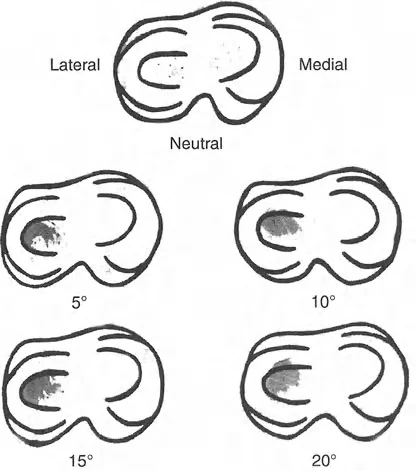

انحراف المحور الميكانيكي (MAD): مقياس الضرر

بناءً على ملاحظات التشريح الطبيعي، تُعتبر مفاصل الطرف السفلي متوازية بشكل طبيعي. أي تشويه لهذه العلاقة يؤثر بشكل متوقع على نقل الأحمال. بينما يمكن لمفصل الورك (كونه مفصلاً كرويًا متطابقًا للغاية) أن يستوعب بعض التغيير في اتجاه الحمل، ومفصل الكاحل محمي بحركة تعويضية معقدة للمفصل تحت الكاحل، فإن الركبة معرضة بشكل استثنائي للتغيرات في المستوى التاجي. إنها مفصل مفصلي يعتمد بشكل كبير على أربطته الجانبية والغضاريف الهلالية لإدارة الأحمال غير المتساوية.

عندما يؤدي تشوه المستوى التاجي إلى اختلال المحاذاة المحورية، فإن محور تحمل الوزن يمر إما وسطيًا أو جانبيًا لمركز الركبة. تُقاس القيمة المطلقة لهذا الانحراف باسم انحراف المحور الميكانيكي (Mechanical Axis Deviation - MAD).

يعكس حجم MAD بشكل مباشر حجم نقل الإجهاد المتغير عبر الركبة. يُعد قياس MAD متفوقًا بشكل كبير على مجرد قياس الزوايا الإجمالية للطرف لأنه يأخذ في الاعتبار التشوهات من أي نوع — بما في ذلك الدوران، الانتقال، والزاوية — ويترجمها إلى قيمة ميكانيكية حيوية واحدة ذات صلة سريريًا.

تأثير مضاعفة القمة (Apex Multiplier Effect)

بشكل حاسم، يأخذ MAD في الاعتبار مستوى (أو ارتفاع) التشوه. يزداد تأثير التشوه الزاوي على المحور الميكانيكي الكلي بشكل كبير كلما اقتربت قمة التشوه من مفصل الركبة. يُعرف هذا باسم تأثير مضاعفة القمة. تشوه زاوي بمقدار 10 درجات في منتصف جسم عظم الفخذ سينتج عنه MAD أصغر بكثير من تشوه بمقدار 10 درجات في الجزء القريب من مفصل الفخذ. لذلك، فإن التشوهات حول المفصل (القريبة من الركبة) تكون أكثر تدميرًا لميكانيكا المفصل وتتطلب تصحيحًا جراحيًا أكثر قوة من تشوهات جسم العظم بنفس الحجم الزاوي.

مبادئ بالي لاتجاه المفصل (Paley's Principles of Joint Orientation)

بعد تحديد محاذاة الطرف السفلي (MAD)، يجب على الجراح تقييم اتجاه المفاصل بشكل منهجي بالنسبة للمحور الميكانيكي. لكل مفصل ميل طبيعي يمكن التنبؤ به بدرجة عالية. تشكل هذه القيم الطبيعية الخطوط والزوايا المرجعية التي تُعد متطلبات أساسية للتخطيط قبل الجراحة ولتحديد مركز دوران الزاوية (CORA).

الهدف النهائي لأي جراحة لتصحيح التشوه هو هدفان:

- استعادة المحاذاة الخطية الطبيعية: القضاء على MAD بحيث يمر المحور الميكانيكي عبر مركز الركبة.

- استعادة اتجاه المفصل الطبيعي: التأكد من أن خط المفصل لكل مفصل يقع بزاوية صحيحة بالنسبة للمحور الميكانيكي، مما يمنع قوى القص التي تدمر الغضروف.